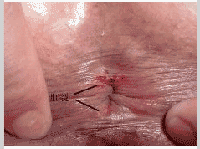

大便肛裂是怎么回事

大便时,粪便刚经过肛门口,感到烧灼样或刀割样剧烈疼痛是不是患了肛裂?排完便纸巾上有血是不是患上肛裂了?很多人都很疑惑,大便肛裂是怎么回事,下面就由洛阳东大专家为大家讲解下。告诉在线医生你的症状,为你分析病情

①外伤:干硬粪便或者异物等损伤肛管皮肤,导致肛裂;

②便秘:长期便秘,导致在排便时出现肛门裂开情况;

③感染:肛裂发病时,会逐渐向下蔓延而致皮下脓肿等感染;

④不良的排便习惯:会加重直肠肛门和盆底肌肉的负担,导致肛裂的发生。拉屎太用力导致肛裂怎么办?